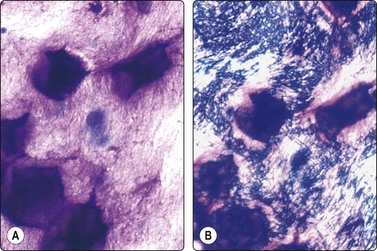

image image

Fig. 14.2 Sarcoid-like foreign body granuloma

(A) Large multinucleated giant cells, clustered histiocytes and some inflammatory cells. Birefringent foreign material present but not seen in this microphotograph (Pap, IP); (B) Corresponding tissue section. Sarcoid-like cluster of many discrete granulomata of epithelioid histiocytes and some giant cells; no evidence of caseation; foreign bodies seen in polarized light (H&E, LP).